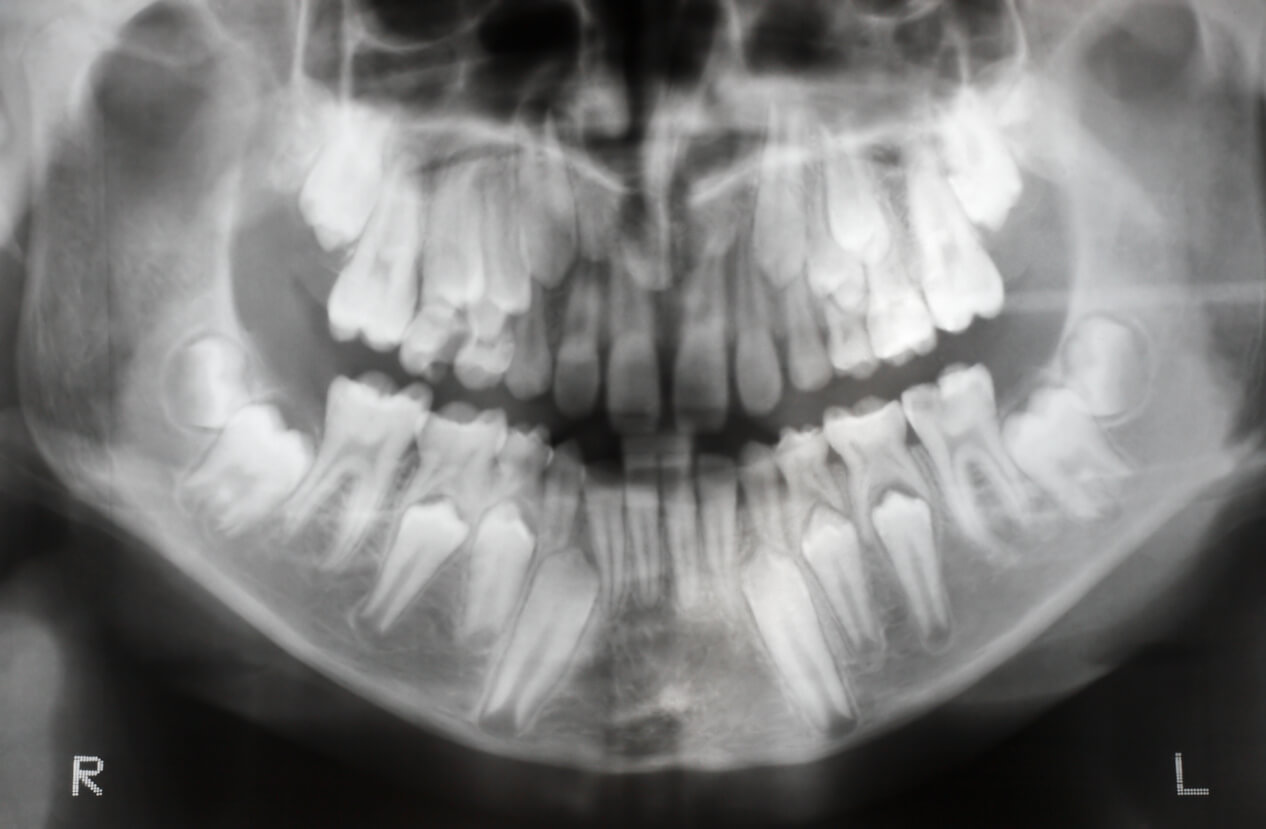

- Ortopantomografía o «radiografía panorámica»: permite observar toda la boca en una sola toma. Con una mínima exposición y un procedimiento sencillo y cómodo, aporta una gran cantidad de datos útiles.